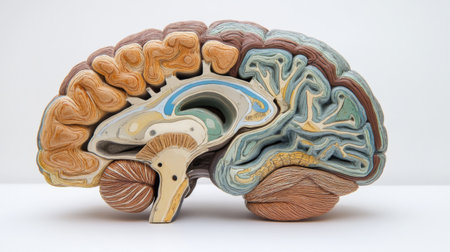

This detailed cross-section of the human brain illustrates its anatomical features, making it ideal for educational purposes in neuroscience and medicine.

An educational scene featuring a human brain cross-section with labeled parts, alongside medical charts and anatomical references for a classroom setting.

This close-up photo captures the intricate details and structures of a human brain, Cross-sectional image of a human brain, AI Generated

An educational scene featuring a human brain cross-section with labeled parts, alongside medical charts and anatomical references for a classroom setting.

An educational scene featuring a human brain cross-section with labeled parts, alongside medical charts and anatomical references for a classroom setting.